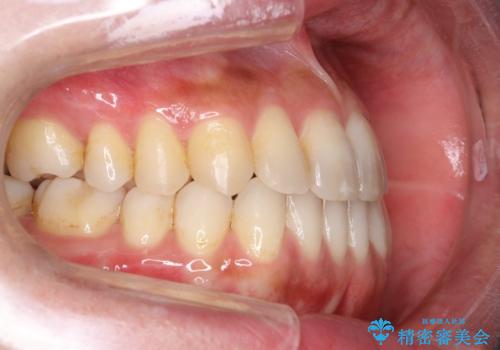

Invisalign インビザライン によるガタつき、受け口傾向の改善

- 拡大・IPRによるスペースゲインを主とした非抜歯・マウスピース矯正を計画しました。

奥歯の位置関係の修正は難儀することが多いマウスピース矯正ですが、割とスムーズに奥歯の位置関係の修正をすることができました。

クロスバイトもきれいになり、きれいな歯並びとなりました。